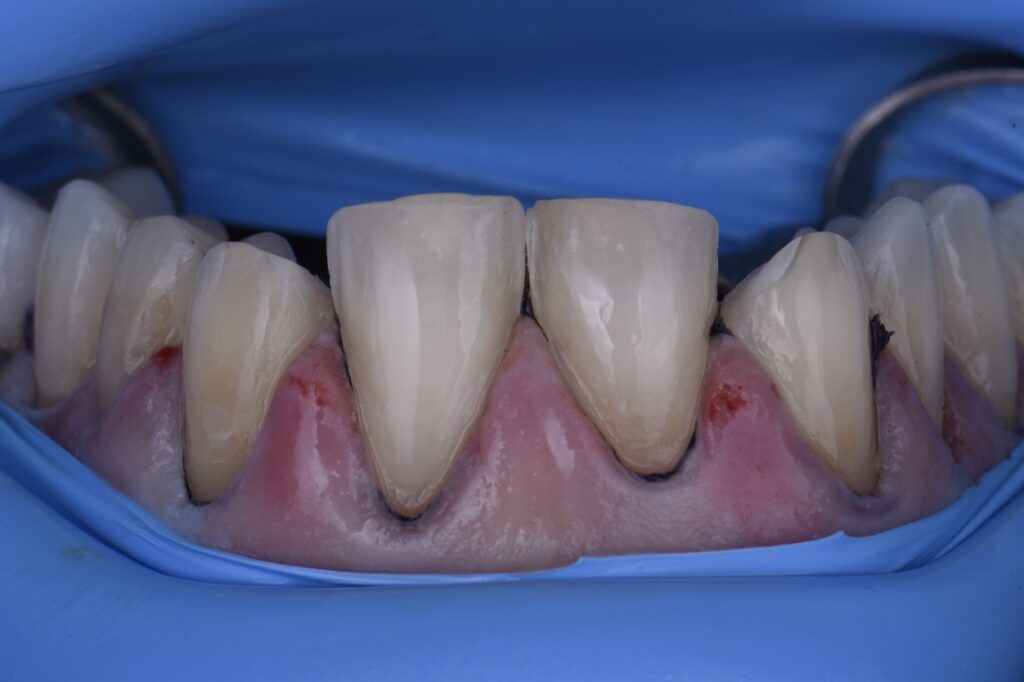

Veneer Preparations and Provisionalization Temporization Temporary Veneer Sensitivity If you experience sensitive teeth after your veneers, there are a few things you can do to minimize your discomfort. In this article, we’ll explore the. This sensitivity should diminish gradually. This may cause some discomfort while chewing or alter. What if you have sensitivity after temporary veneers? But what causes tooth sensitivity after the veneers procedure, and should temporary. Temporary Veneer Sensitivity.

Clinical case Central incisor veneers with PANAVIA V5 Temporary Veneer Sensitivity They act as a protective barrier, shielding your sensitive tooth structure from potential damage, sensitivity, or contamination. But what causes tooth sensitivity after the veneers procedure, and should temporary veneers cause pain? Temporary porcelain veneers can be sensitive. If you experience sensitive teeth after your veneers, there are a few things you can do to minimize your discomfort. What if. Temporary Veneer Sensitivity.